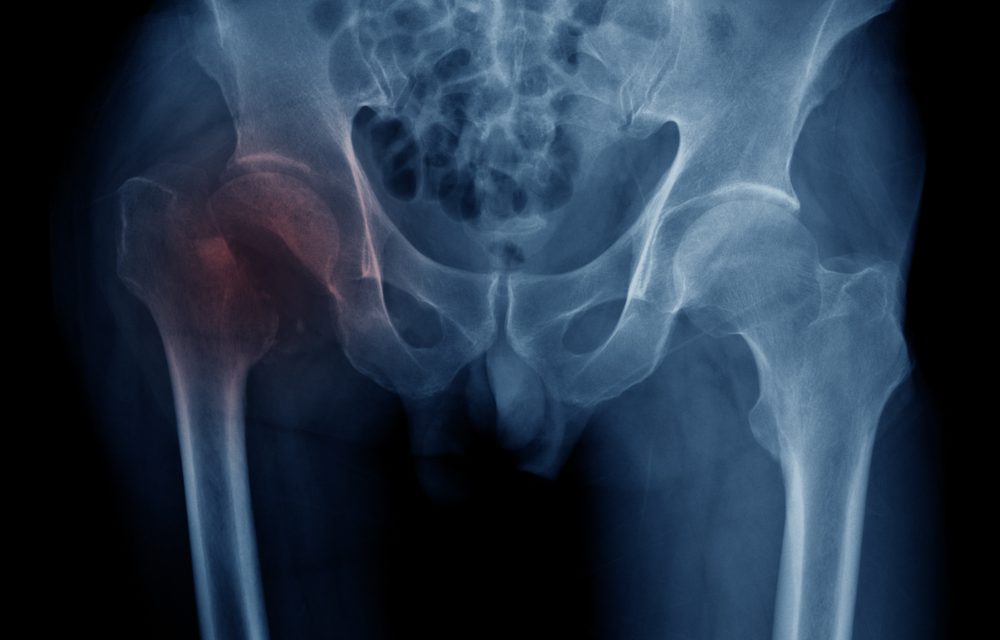

The analysis found that calcium supplementation at doses of approximately 300 mg per day did not reduce the risk of hip fracture. Even in clinical trials using higher calcium intakes—between 800 and 1,600 mg per day—no significant reduction was seen in hip fractures or other non-vertebral fractures.